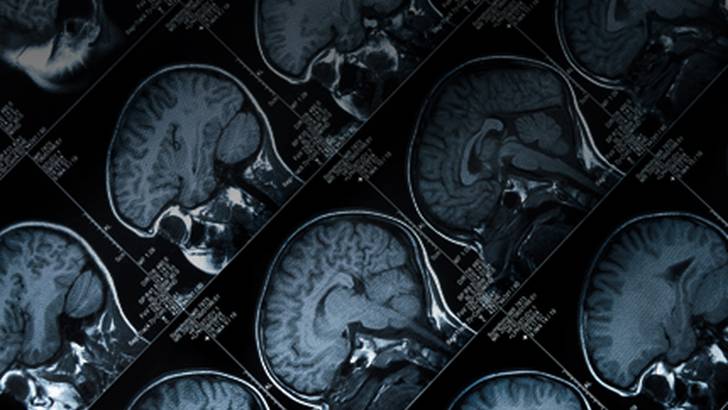

There are two causes of death in sports: cardiac and neurological. Dr. Jeffrey Kutcher joins host Dr. Anthony Alessi to explore the neurological causes of sudden death in sports. Dr. Kutcher is associate professor of neurology at the University of Michigan, director of Michigan NeuroSport, a multidisciplinary center dedicated to the evaluation and management of neurologic sports injuries, and chairs the sports neurology section of the American Academy of Neurology.